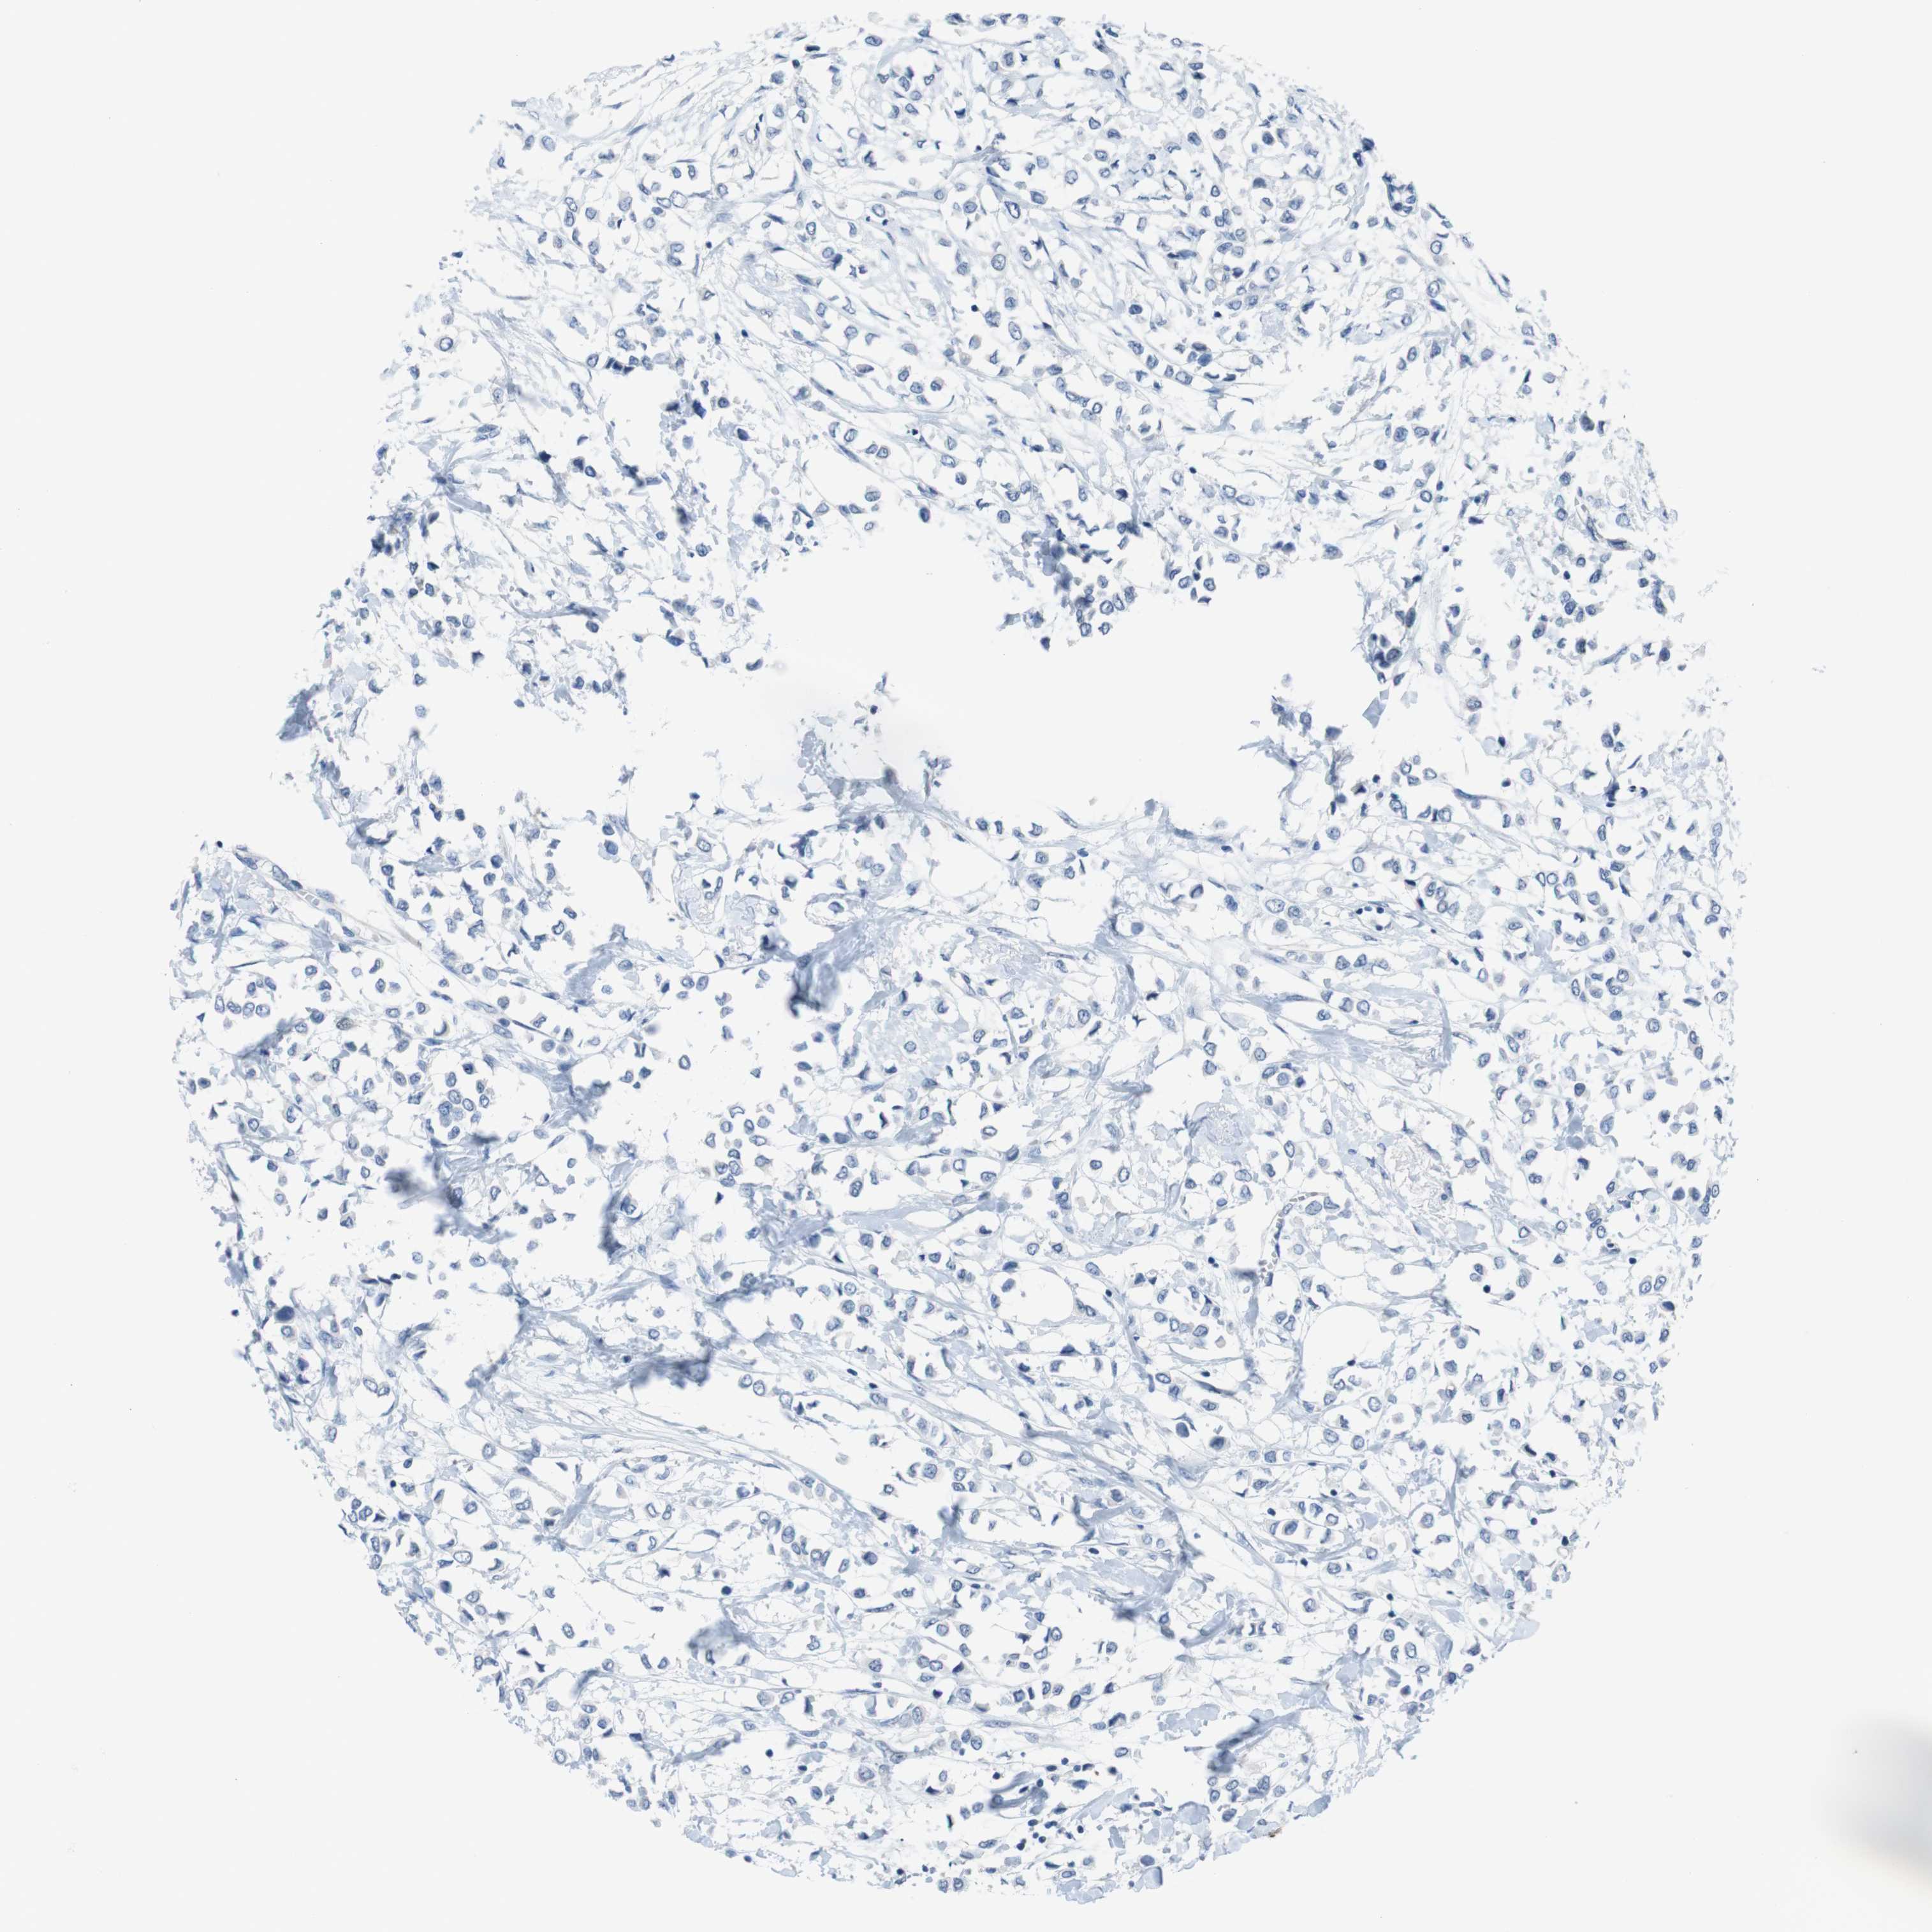

BRCA TCGA BRCA VALIDATION PROTEIN EXPRESSION

ANTIBODIES

AND

VALIDATION